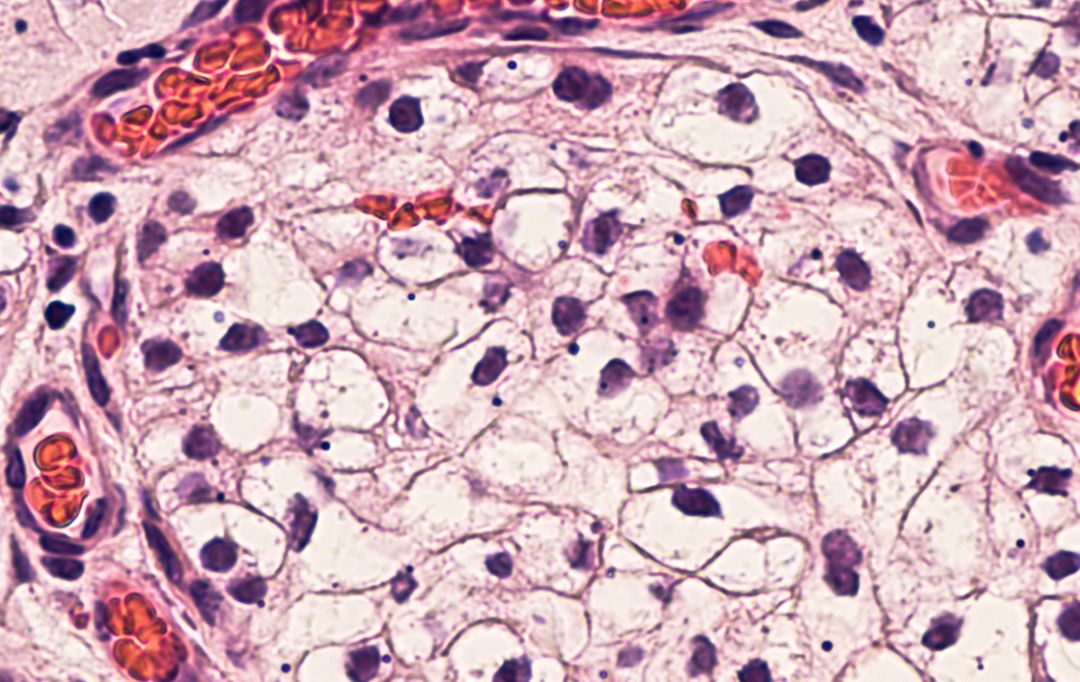

治疗显示,静脉内注射的MSCs能够迁移到急性和慢性肾损伤模型动物的肾小球、肾间质、小管周围血管和肾小管。

干细胞植入体内后,通过干细胞的自动归巢作用,干细胞会自动转移到肾脏病灶,分化生成所需的各类细胞,从而达到修复肾脏固有细胞,恢复肾功能,重建肾脏血液循环,阻断和逆转肾脏纤维化进程。   近年来干细胞在治疗肾病过程中发现,干细胞可分化成肾固有细胞,肾实质细胞等,所以干细胞移植后对肾脏功能具有良好的修复和重建作用。